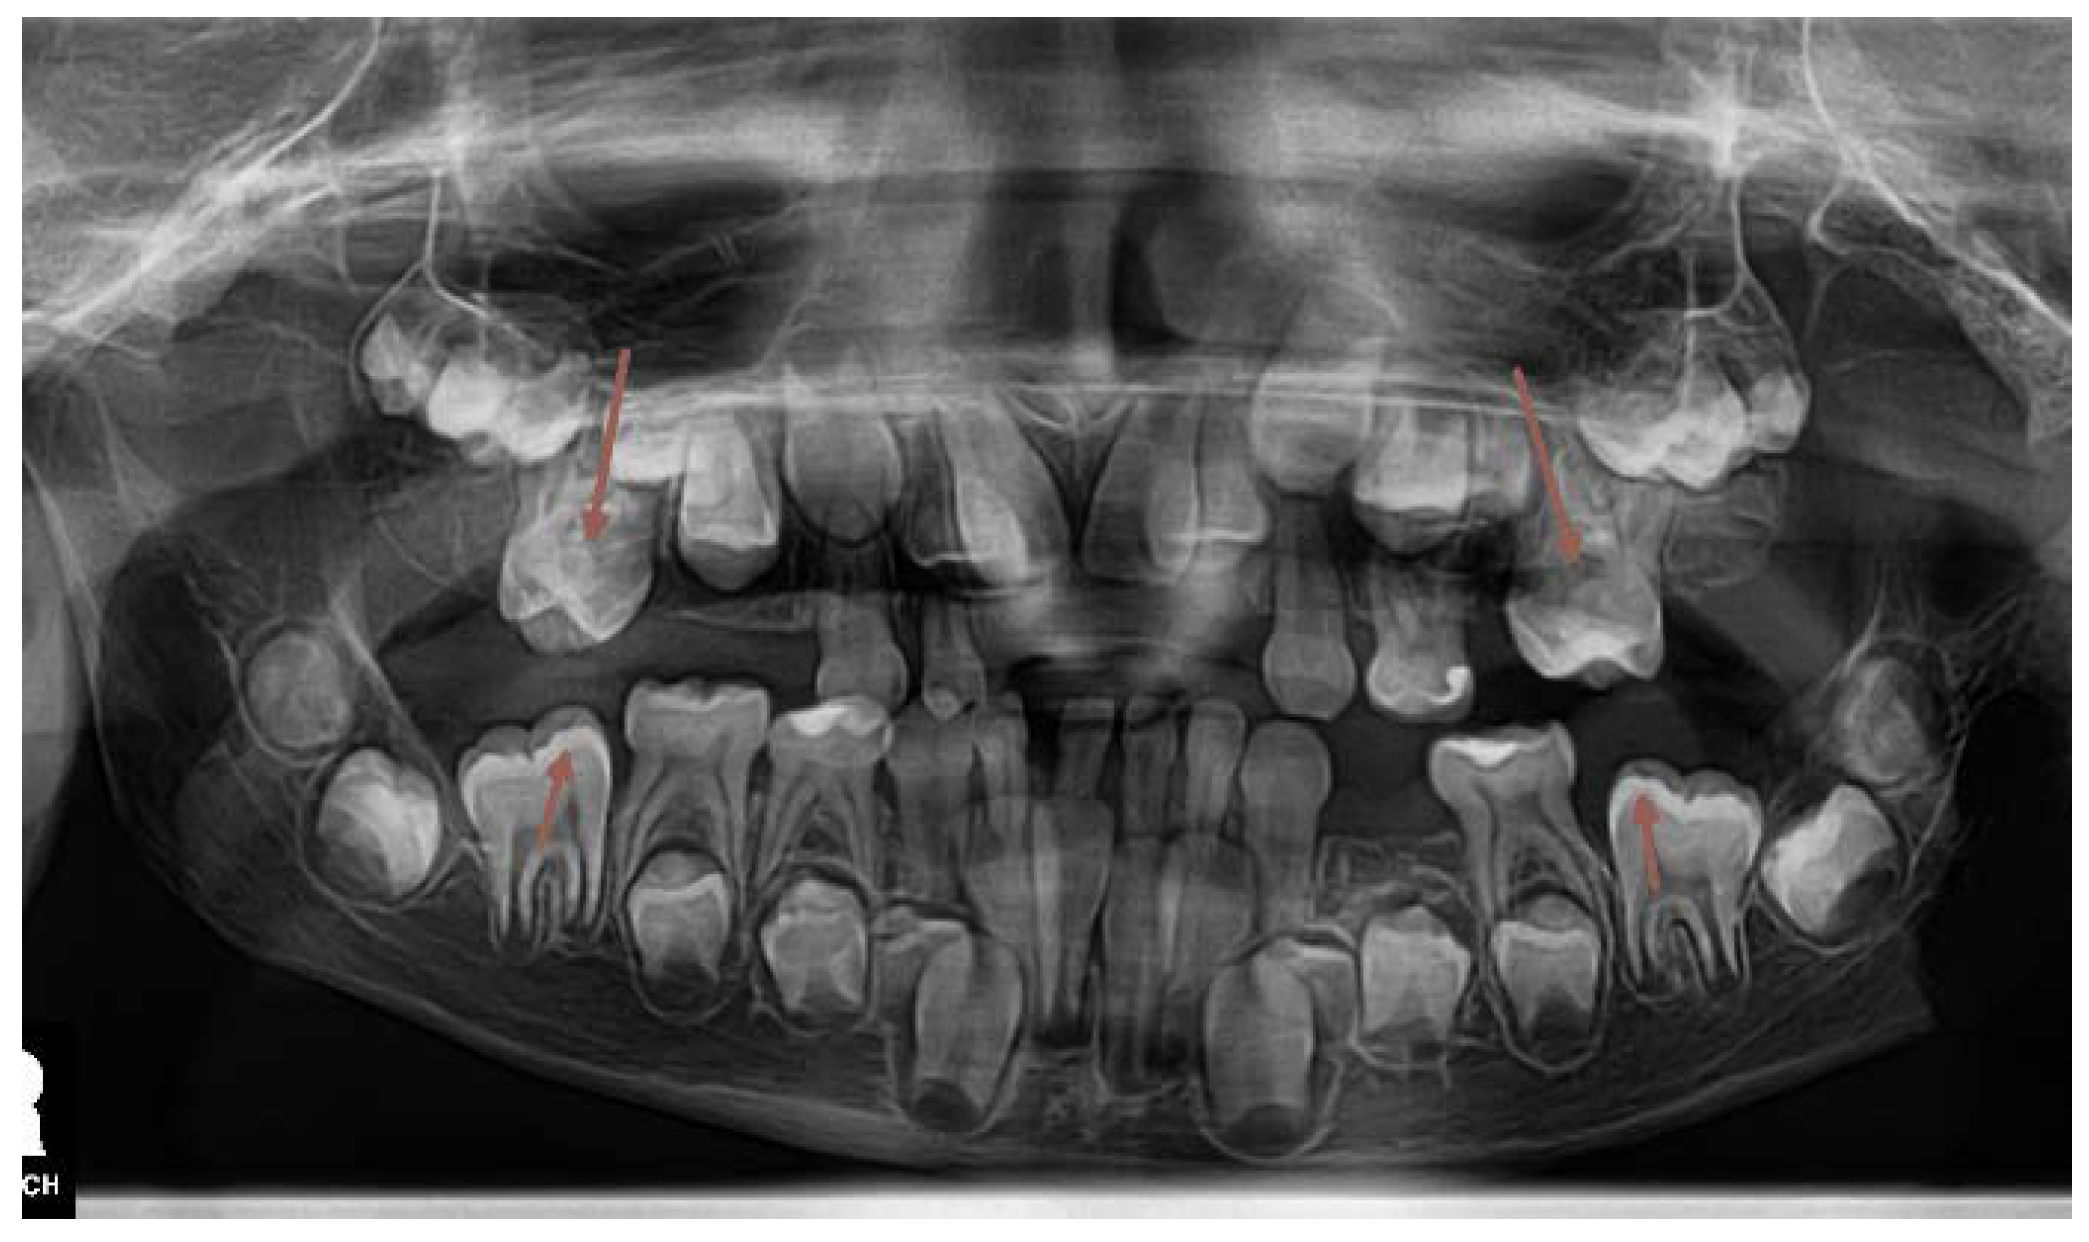

On the panoramic radiographic image (OPG) taken in April 2013 (Figure 1.) there was a finding of over-retained deciduous teeth with unresorped roots. The dental age was estimated according to the Demirjan method, 4,6 years in the upper dental arch and 6,9 in the lower. Three supernumerary teeth were present in the upper jaw, and two in the lower, displacing the developing permanent teeth and obstructing their eruption. All regular permanent teeth buds were in place, some of them were retarded in eruption also because of a lessened eruptive potential. There was a serious (approximately 3 years) delay in the root development of the permanent teeth. The dental age was estimated according to the developmental stages of the roots of permanent teeth and resorption stages of deciduous predecessors – the Demirjan method [19,22].

The three-dimensional (3D) reconstruction of the CBCT x-ray, taken in May 2013 revealed three more supernumerary empty tooth crypts in the upper jaw and proved the two supernumerary teeth in the lower. The patient had had 8 supernumerary teeth at that time. (Figure 1.,6.,7.)

Two surgical interventions in general anesthesia were planned in the upper jaw, provided that no more supernumerary teeth develop from empty, non-mineralized supernumerary dental crypts, which are usually difficult to localize on early CBCT scans. One surgical intervention under general anesthesia was planned in the lower arch to extract the two supernumerary teeth in the premolar area. (Figure 1)

Figure 1. The initial OPG x-ray of the patient (2013).